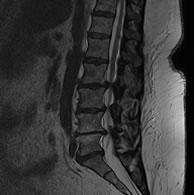

El canal estrecho lumbar consiste en la reducción del diámetro del canal espinal y/o sus forámenes en la región lumbar. Puede presentarse como un canal estrecho central, lateral o mixto. Es producto de un proceso degenerativo relacionado con el envejecimiento.

• Resonancia Magnética de columna lumbar, permite evaluar las deformidades del saco dural, así como la presencia de discopatias y la permeabilidad de los forámenes de conjunción.